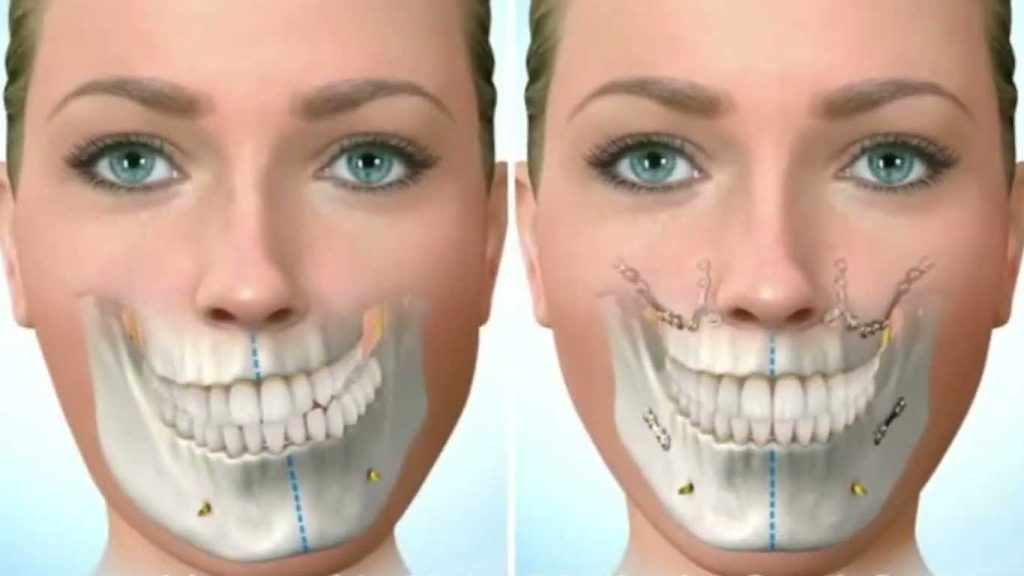

درمان ارتودنسی به همراه جراحی دو فک در اصلاح فک های نامتقارن شدید که نیاز به تغییر موقعیت هر دو فک دارند، استفاده می شود.

جراحی ارتوگناتیک:

در موارد شدید که استخوان فک به طور قابل توجهی نامتقارن است، ممکن است جراحی برای اصلاح ساختار فک ضروری باشد.

در بسیاری از موارد شدید فک نامتقارن، درمان ارتودنسی به همراه جراحی فک می تواند به تصحیح ناهنجاری کمک کند.